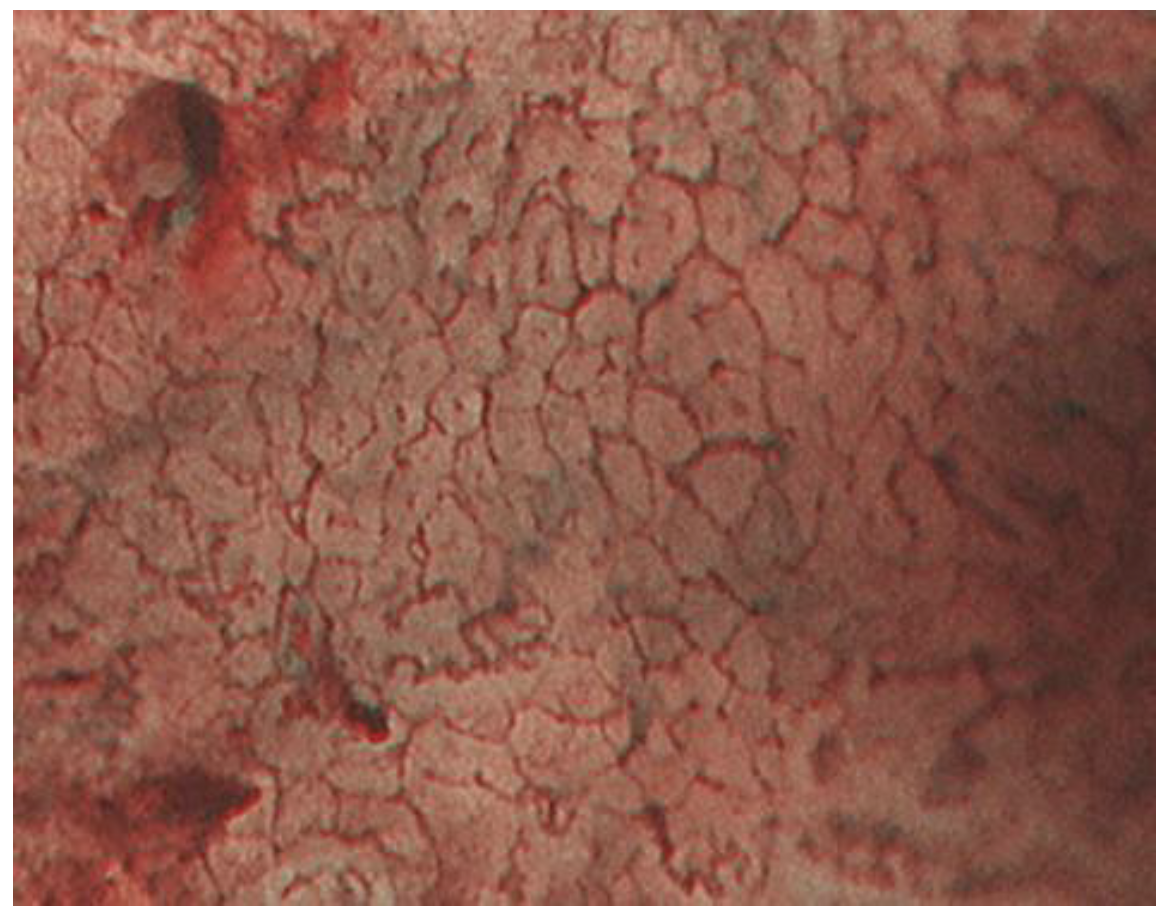

2.1. ME-NBI for Gastric Non-Cancerous Mucosa